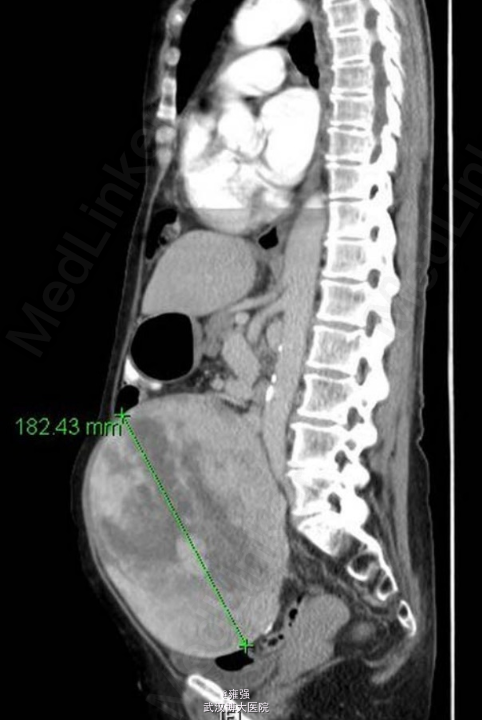

辅检:肿瘤标记物(CEA、CA19-9、CA125)均在正常范围,入院后腹部X片示下腹部出现增强的不透光区(如下图示)。术前TAP分段CT示盆腔内大型、界限清楚、中线测量为 18.8 cm×13.3 cm×18.2 cm、混合衰减的包块(如下图示),位于子宫前、膀胱之上,独立于子宫存在,考虑为起源于卵巢。